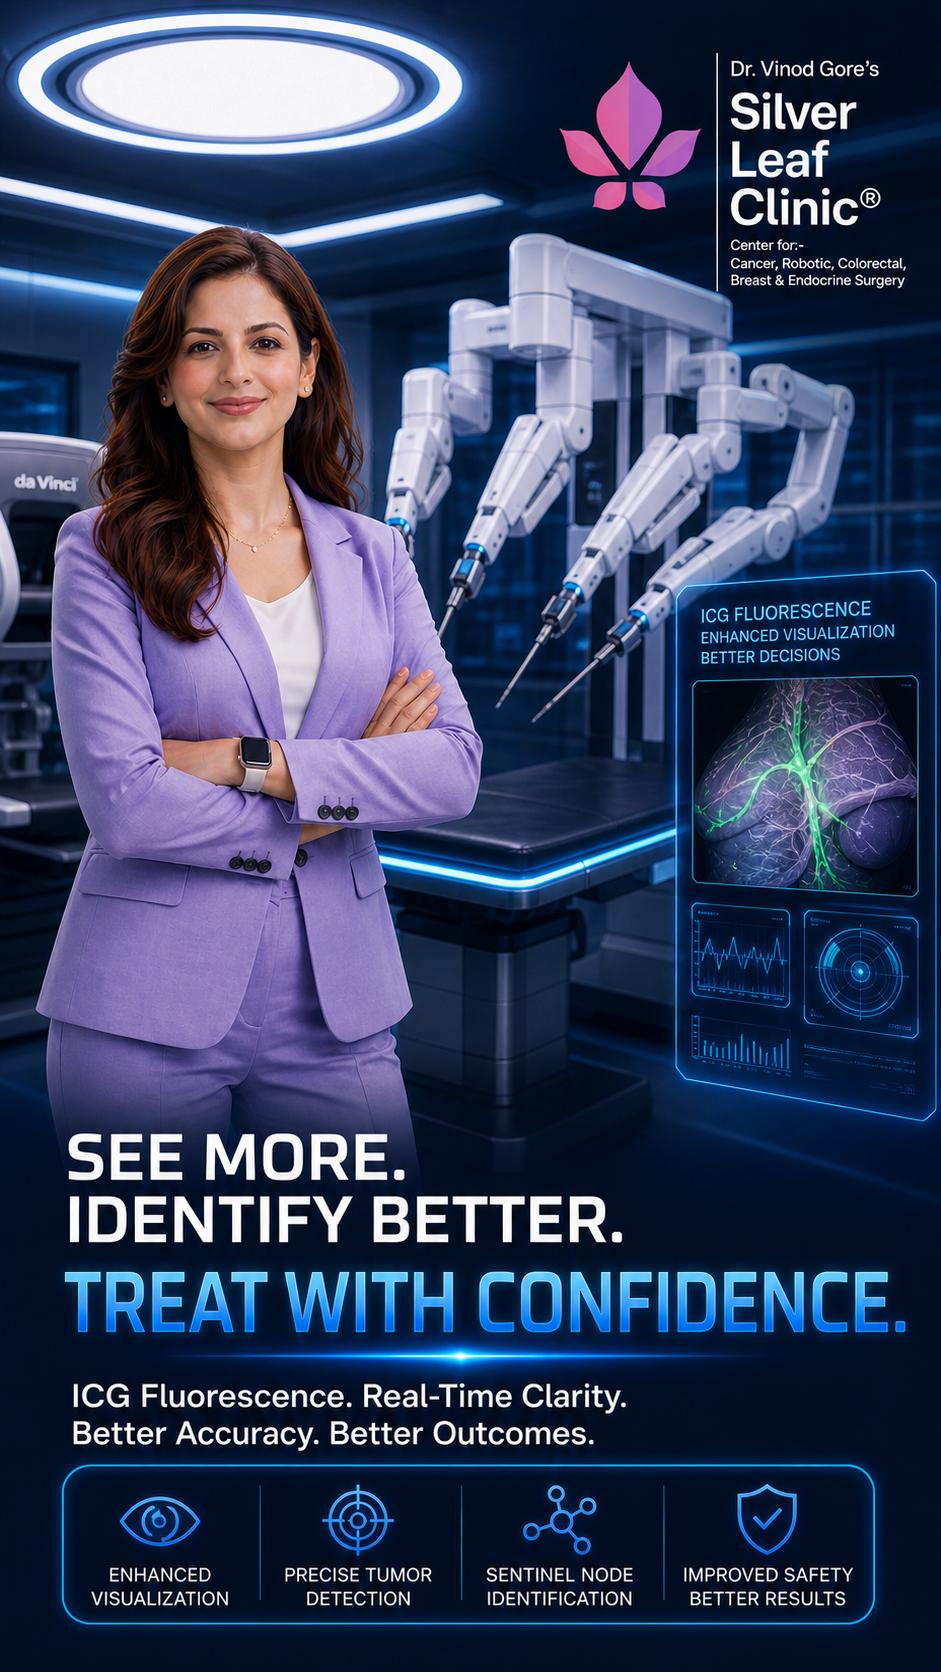

Don't Miss the Signs. Trust Robotic Precision

Take step confidently into a healthier future

Prioritize your well-being today